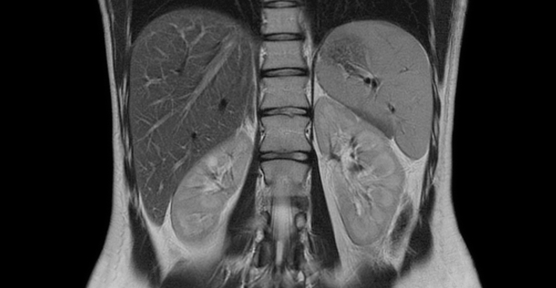

M.R.I.

Magnetic resonance imaging (MRI) is a test that uses a magnetic field and pulses of radio wave energy to make pictures of organs and structures inside the body.

Siemens MAGNETOM Spectra a state of art 3Tesla MRI imaging for broad realm of clinical applications and access to premium clinical care. Ultra-Short MRI system – head out in most exams for anxious patient Light weight and ergonomically designed open architecture coils with smooth connection – less claustrophobia experience.